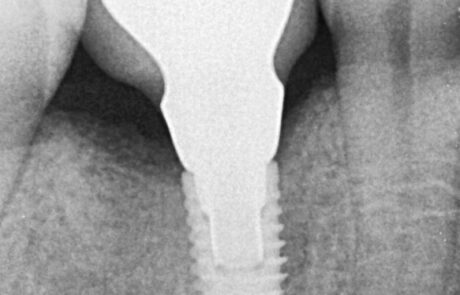

Implantología Bucomaxilofacial

Corona sobre implantes o piezas dentales